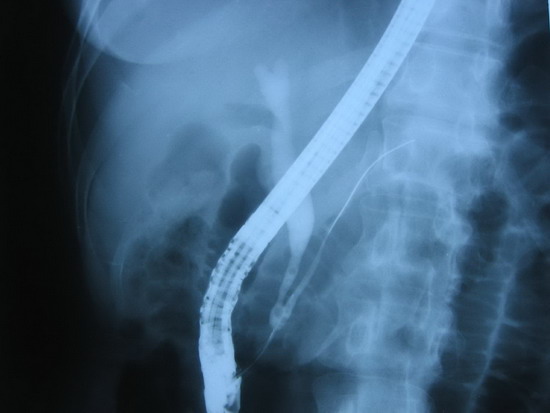

ERCP(2006年5月25日):

乳头插管成功后造影,见胰胆管汇流异常,为B-P型,共同段长约1.5厘米,共同通道膨大,乳头开口狭窄,近端胆总管轻度扩张,横径约1.2厘米。留置导丝后行共同段括约肌切开0.8厘米,插入取石球囊,充气后拉出一些存在于扩张的共同段内的灰白色絮状物。